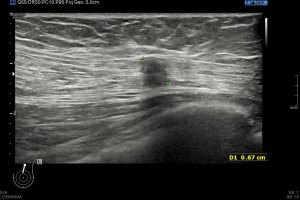

Si colocas la sonda en el mentón, en axial vas a encontrar este músculo Digástrico, que se verá muy bien, superficial, en un plano intermedio tendrás el músculo Milohiodeo y en la profundidad los músculos Geniohideos, Geniogloso y el Hiogloso…Mira:

El Músculo Milohioideo se encuentra en un plano medio, es fino y separa el plano superficial muscular, del profundo, en la imagen superior ves una pequeña porción de este músculo. En el plano profundo un grupo de varios músculos, que he mencionado más arriba y que son músculos extrínsecos de la lengua, situados en la región más medial de esta localización submentoniana estudiada.

Los vientres anteriores de los músculos Digástricos, que son el objeto del desarrollo de este Post, son dos estructuras musculares redondeadas en el corte transversal, imagen 1, y alargados si los estudiamos en el eje largo, imagen 3, mira:

Ecográficamente los músculos digástricos en eje corto tienen semiología hipoecogénica, en aspecto de noche estrellada, como la de hoy, y en el eje largo en forma de penacho o en forma de plumas con las fibras alargadas y paralelas a la superficie.